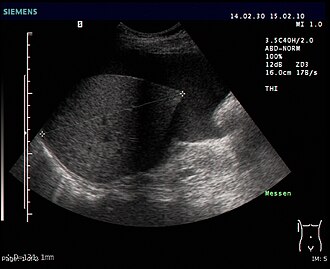

Dijagnoza uzroka počinje pretragama krvi, ultrazvukom abdomena i izravnim uklanjanjem tekućine iglom ili paracentezom (koja također može biti terapeutska). Algoritam dijagnostike bi izgledao kao što je navedeno:

- Ultrazvuk: Manja količina se ovim pregledom može vidjeti ispod jetre ili u Douglasu. G